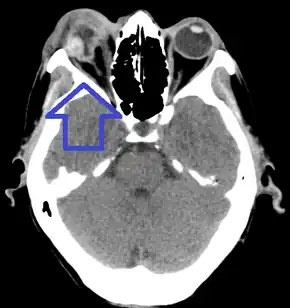

Globe rupture seen on CT scan

On CT scan, signs of global rupture include: deepening of the anterior chamber, alteration of global contour with scleral folds, discontinuity of scleral folds, and a shrunken globe.[6]